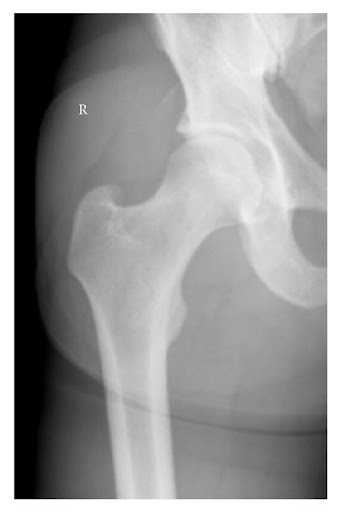

Bệnh nhân nam 38 tuổi tiền sử khỏe mạnh bị trật khớp háng (phải) về phía trước. Tai nạn xảy ra sau khi bệnh nhân sút bóng bằng chân phải, trong tư thế khớp háng phải xoay ngoài. Anh ta cảm thấy tiếng “pop” và ngã sấp. Sau tai nạn chân phải không thể chịu lực. Bệnh nhân khai không có va chạm với cầu thủ khác. Khám lâm sàng thấy chân phải xoay ngoài, không có điểm đau chói. X-quang xương chậu (thẳng) cho thấy trật khớp háng phải

Chụp X quang xương chậu thẳng cho thấy hình ảnh trật khớp háng (Phải)